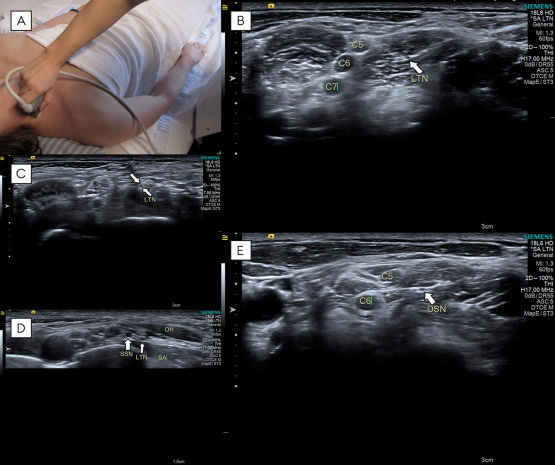

Nervio torácico largo (LTN) y nervio dorsal de la escápula (DSN).

Todas las imágenes ecográficas corresponden al lado izquierdo en un sujeto sano.

A) El transductor se colocó en el cuello, sobre o por delante del músculo esternocleidomastoideo.

B) LTN1: El nervio torácico largo (LTN) (flecha blanca) se identifica en o por debajo del músculo escaleno medio, en su punto de mayor calibre, discurriendo dentro de una línea fascial hiperecogénica.

C) LTN2: El LTN (flechas blancas) se visualiza por encima de la musculatura escalénica, en su punto de mayor calibre.

D) LTN3: El LTN se observa por encima del músculo serrato anterior (SA), por debajo del músculo omohioideo (OH) y anterior al nervio supraescapular (SSN), en su punto de mayor calibre.

E) El nervio dorsal de la escápula (DSN) (flecha blanca) se identifica dentro del músculo escaleno medio, en su punto de mayor calibre, también discurriendo en una línea fascial hiperecogénica.